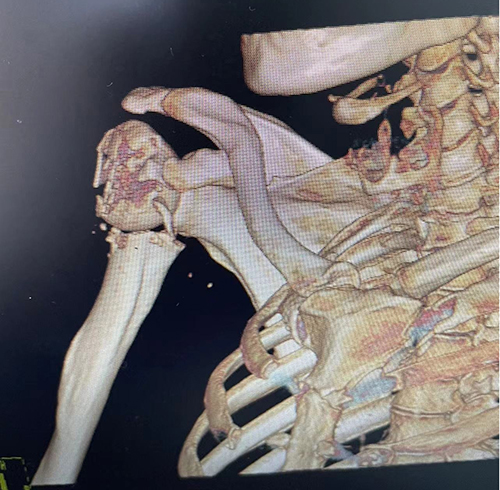

观片灯前,罗令仔细端详着片子,CT显示老李右肩骨折后肱骨头明显翻转,微创手术有较大难度。在患者的信任与期待中,湘雅三医院创伤骨科一直坚守“能保守治疗就不手术,能微创就不切开”的信念,选取最有利的手术方案。因此尽管微创难度大,但对患者而言康复更快,并发症更少,哪怕有一线希望也要帮患者争取。

▲术前CT检查